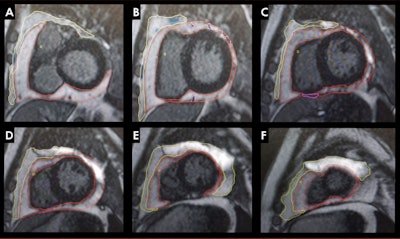

Maishi and colleagues wanted to study such prevalence in people living with HIV who also undergo antiretroviral therapy use. They wanted to quantify pericardial adipose tissue and paracardiac adipose tissue in patients by using 3T cardiovascular MRI. Additionally, they wanted to explore the potential relationships between these tissues and other factors such as HIV disease duration, therapy regimen, deformational characteristics, inflammation, and fibrosis.